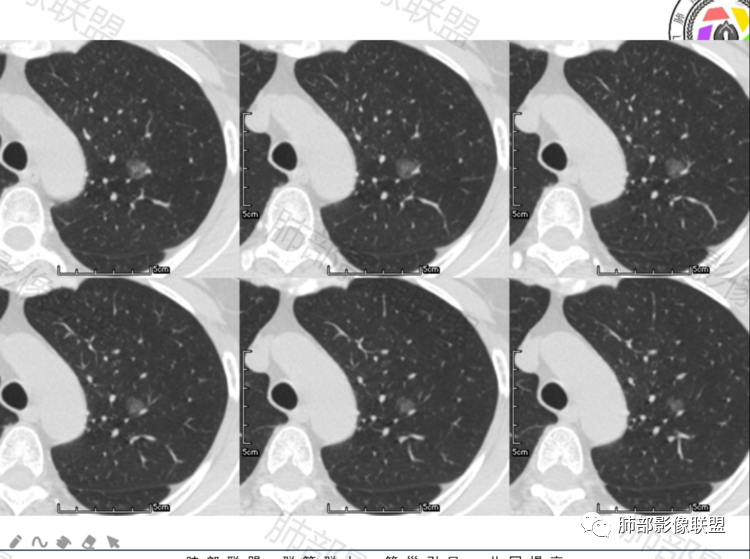

晨读,病例一:左肺磨玻璃结节,边缘清楚,内部有血管穿行自然,有低密度空泡?支气管?10个月后复查,结节增大0.2CM,不排除误差,考虑良性结节或炎性结节,继续短期随访。

病历二:左肺磨玻璃结节影,边界清楚,内部血管穿行,考虑炎性结节或良性结节,继续短期随访。

病例一中年男性,左肺上叶纯磨玻璃结节,边界稍清,内部血管增粗,考虑炎性结节或AIS,建议抗炎治疗后三个月随访。

病例二老年女性,左肺上叶纯磨玻璃结节,边缘清楚,有月牙铲?内部有稍高密度影,血管增粗,考虑微浸润癌MIA,建议密切随访,一个月复查。

这两个病例都是偶发肺内孤立结节,以磨玻璃密度为主,无明显实性成分,边界清晰,并且都经过长期(10-14个月)随访复查,病灶整体大小、形态、密度变化不明显。

两例最终都选择了手术,病例1结果:局灶性肺纤维化;病例2结果:浸润性肺腺癌。